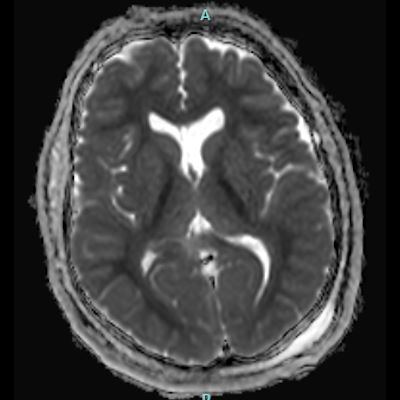

66 yaş, E

Kardiak arrest, 10 dk CPR öyküsü

15.03.2025

24.03.2025